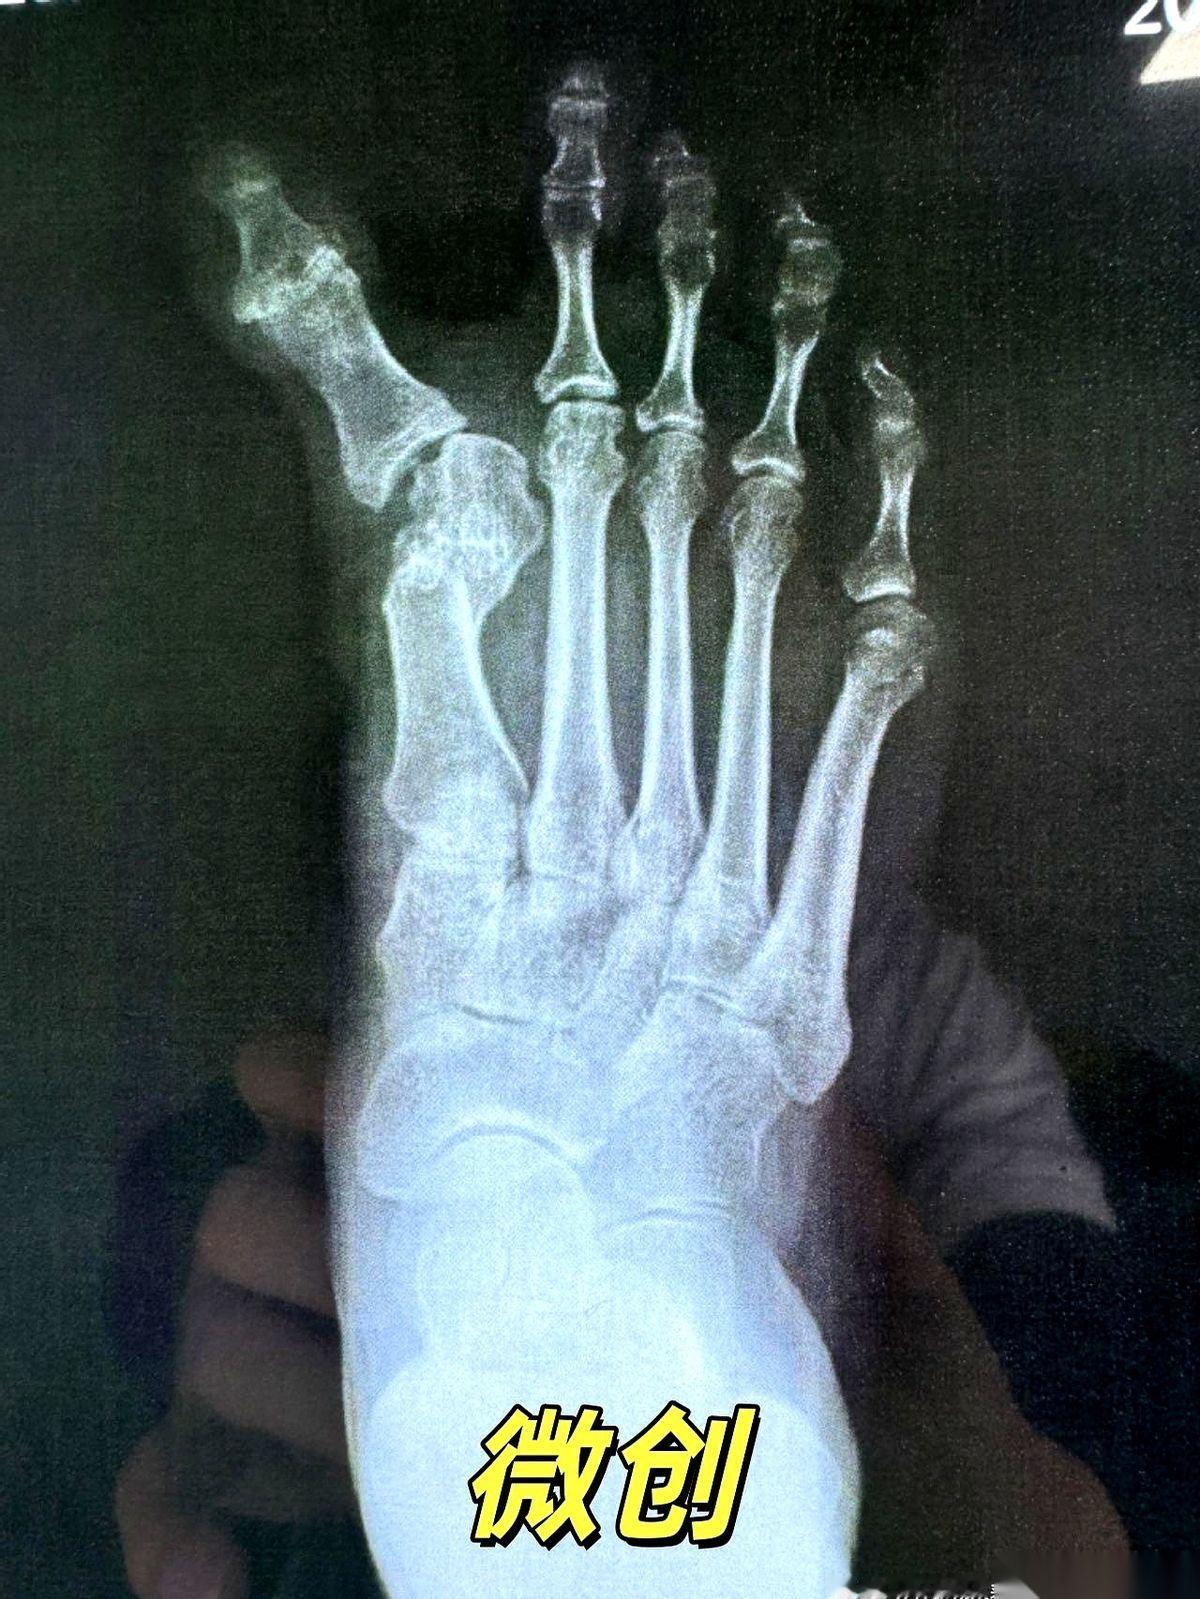

我跟你说,最狠的营销,就是把一个明明需要“伤筋动骨一百天”的事儿,包装成“随做随走”的下午茶。 拇外翻手术就是个典型的例子。 广告里,美女穿着高跟鞋,优雅地走出诊所,好像只是去修了个指甲。 但现实呢?现实是骨头被截断了,是真刀真枪地在你脚上动了刀子。 然后有人信了,真的去了。术后疼得龇牙咧嘴,脚肿得跟个馒头似的,跑去问医生。 医生云淡风轻一句:“挺好的,正常恢复。” 正常个鬼啊。 骨头断了,你拿什么固定?就靠外面绑个绷带? 这就好比房子的大梁歪了,你不用钢筋水泥去加固,反而在墙上贴了个“请勿靠近”的条子,指望它自己长结实? 做梦呢。 “不打钉”听起来好像多高级,多微创。 说白了,很多时候就是省事儿,但风险全留给了你。 骨头长歪了,畸形复发了,甚至得二次手术再遭一遍罪,这些广告里会说吗? 所以啊,别再被那些“不打钉、随做随走”的漂亮话给忽悠了。 下次你再咨询,就直接问那个最根本的问题: “医生,我这截断的骨头,您打算怎么让它稳稳当当地长好?” 看他怎么回答。 身体是自己的,不是试验田。任何手术,都得尊重最基本的生理规律。 捷径的尽头,往往是更远的路。